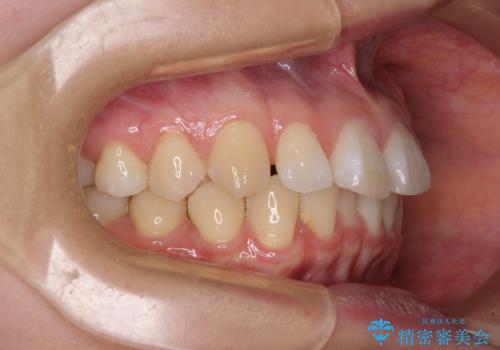

- 上顎前歯の隙間を気にして来院された患者様です。

下顎前歯が上顎前歯に食い込むような咬み合わせにより、上顎前歯が開いてしまっていたため、咬合高径の挙上により突き上げを改善するよう、インビザラインにより矯正治療を行うこととしました。

咬合高径の挙上により上顎前歯の突出感も改善することができ、整った口元となりました。